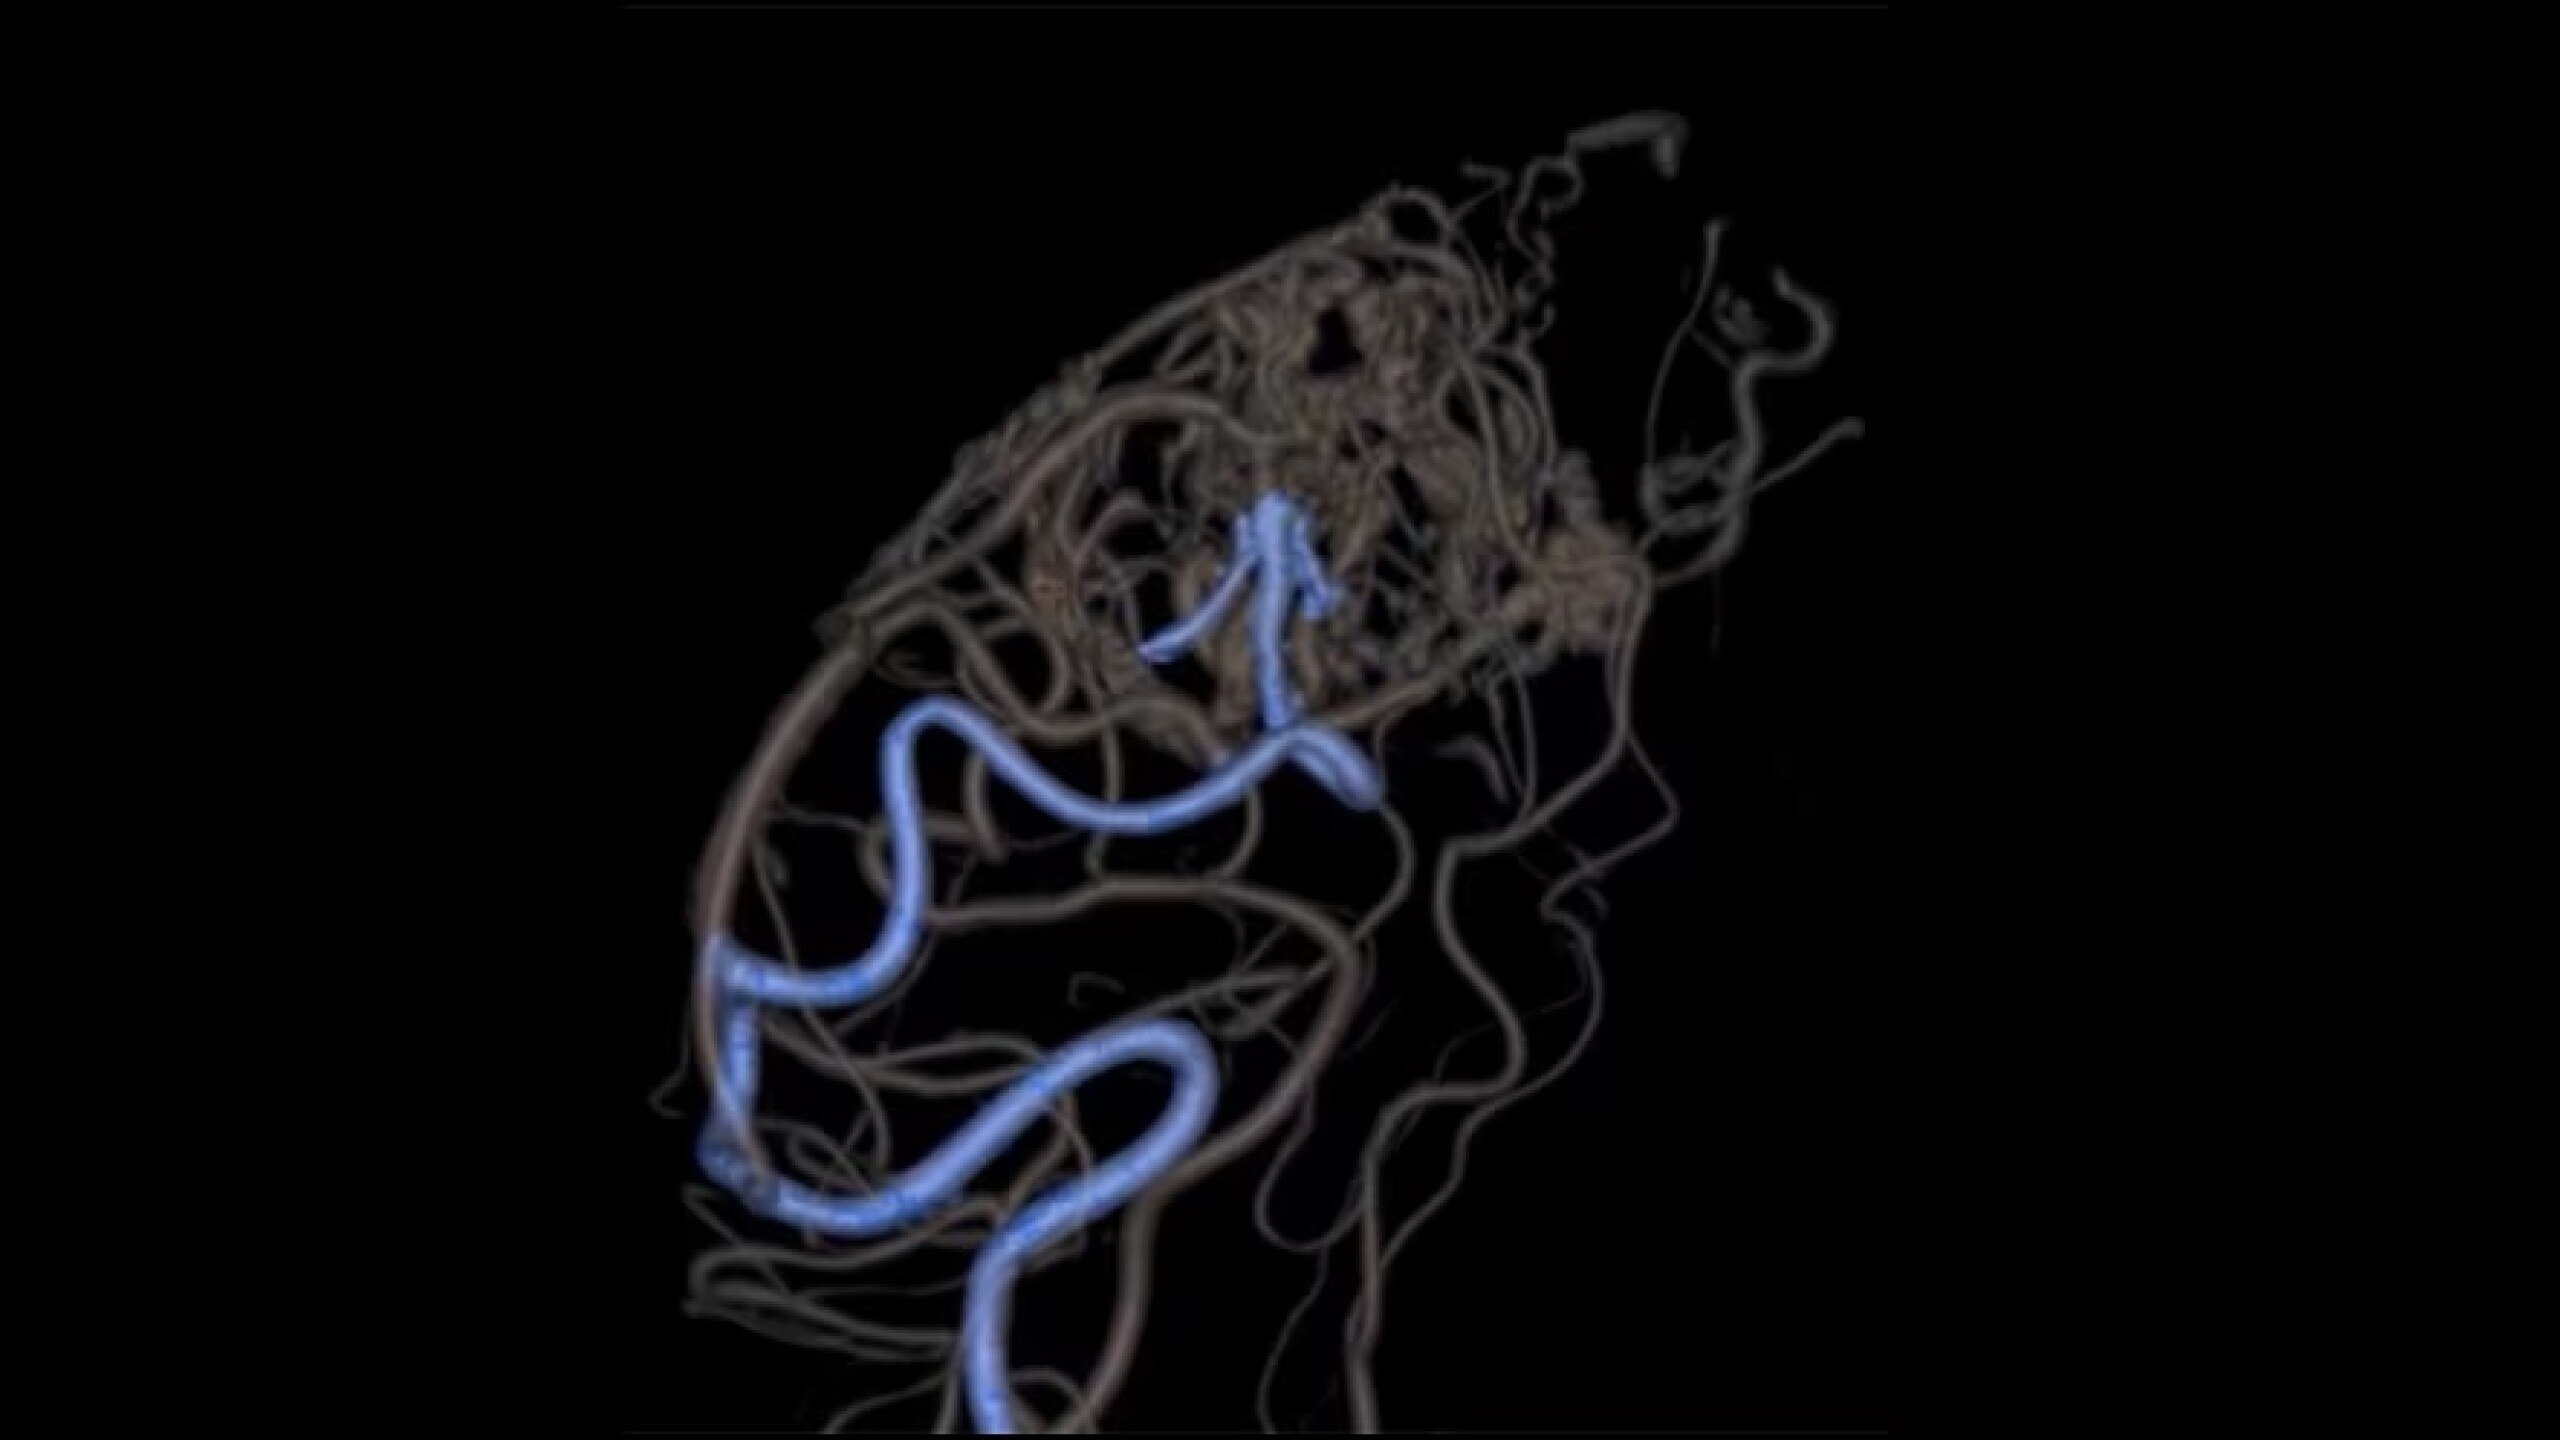

Embo ASSIST is an AI-based augmented guidance solution designed to define optimal embolization strategies and streamline your clinical workflow.

Dynamic simulation at different injection points

Visualize multiple vessels and navigate in cross sections to facilitate planning